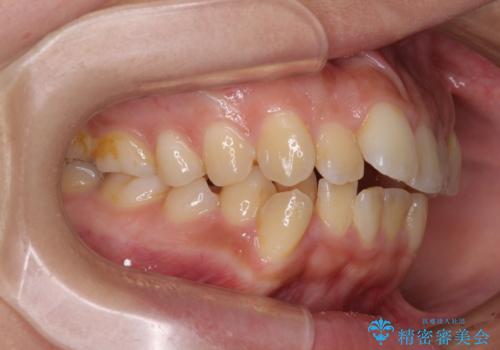

奥歯の噛み合わせは正常に近い状態でしたが、右上の奥歯に突起があったり、上下前歯が非接触であったりしていたため、補助装置を使用して上顎前歯を積極的に引っ込めるように計画しました。

口元の突出感を改善するために上下左右の小臼歯4本を抜歯し、ワイヤー装置によりデコボコを解消しながら口元の突出感も改善していくこととしました。

上下の前歯が接触する仕上がりとなったので、横顔の印象が大幅に改善されました。